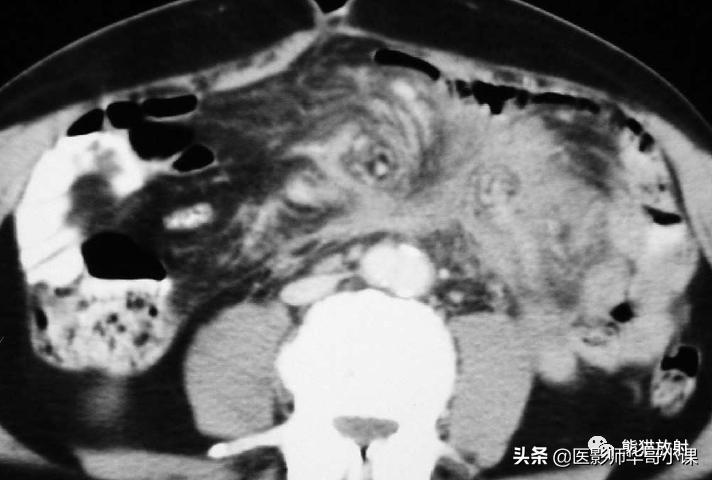

肠系膜脂膜炎的特征性CT表现 为肠系膜根部边界清晰、密度不均的脂肪肿块,包绕肠系膜血管,可推移或不推移邻近肠襻,但不侵犯邻近肠襻,血管周围可见低密度环(图)。T2WI上呈低信号包膜,静脉注射对比剂后可见强化。

肠系膜脂膜炎。患者腹痛,增强CT(A)和真实稳态进动快速成像(true-FISP) MRI(B) 显示一个边界清晰的脂质肿块(大箭),从小肠系膜根部向左侧腹部延伸,包绕肠系膜血管,无扭转。关注血管周围的晕环(小箭)